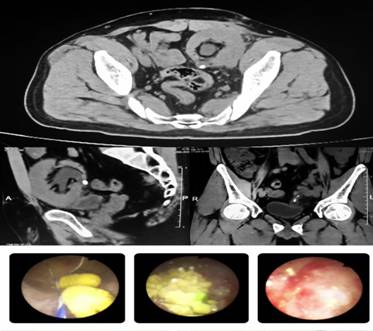

5月23日,在麻醉科、手术室的配合下,在充足术前准备下,李智斌副主任、陈波朋医生为患者施行输尿管镜下移植肾结石钬激光碎石术,术中明确有输尿管狭窄,行输尿管狭窄段扩张后利用钬激光将两枚结石粉末化,再用注射器抽吸,将结石顺利清除干净,避免结石残留。